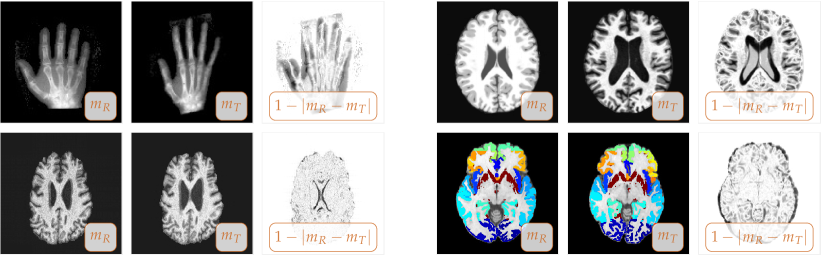

Fig. 1: Real-world two-dimensional registration problems. We display (from left to right) the reference image mRsubscript𝑚𝑅m_{R} (fixed image), the template image mTsubscript𝑚𝑇m_{T} (image to be registered), and a map of the residual differences between mRsubscript𝑚𝑅m_{R} and mTsubscript𝑚𝑇m_{T} before registration (for each set of images as indicated by the inset). Top left: benchmark registration problem [2, 65, 67]; top right: intersubject registration problem; bottom left: longitudinal (intrasubject) registration problem; bottom right: intersubject registration problem [21] (for the latter data we have a ground truth based on annotations: segmentations of 32 anatomical gray matter regions of interest; we overlay the associated label maps onto the reference and template image).